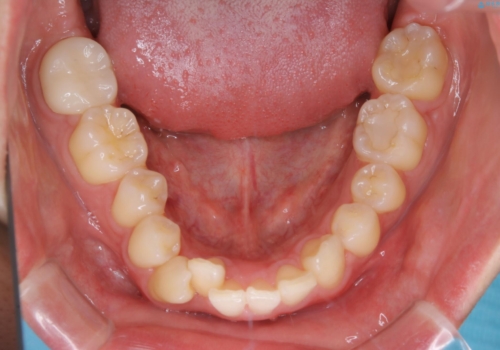

- 口元の突出感は気にならないが、上の前歯の角度と、下の前歯のがたつきが気になるとご相談にいらした方です。なるべく費用や治療期間を抑えて治療したいとのご希望に合わせて治療を計画しました。

この患者様への治療方針として、奥歯から少しずつ歯を移動させる方法と、歯をわずかに削って並べる方法とをご提案しました。短期間での治療を望まれたため、歯をサイズダウンさせて歯を並べました。わずかではあるものの、削った歯は元には戻せないことを十分ご説明し、ご理解ご了承を頂いた上で治療を行いました。